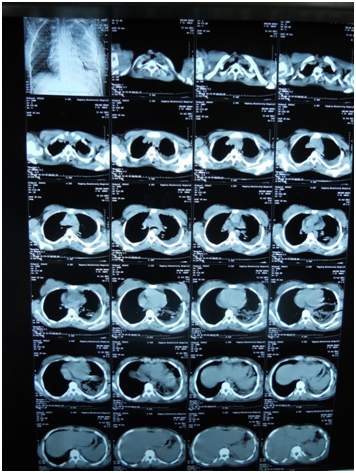

A 17-year-old girl (170cm, 60kg) presented to the emergency department with dyspnea and chest pain after a penetrating stab wound to the chest in the left sixth intercostal space mid-clavicular line, which happened 2hours earlier. Upon physical examination, Pulse was 96 beats per minute and blood pressure was 110/70mmHg, diminished air entry was noticed on the left side of chest. Chest x-ray revealed left hydropneumothorax. Tube thoracostomy was performed left intercostals tube was inserted for drainage. Post-insertion chest x-ray revealed no improvement in the picture of air fluid level (Figure 1) (Figure 2) which was further evaluated by CT that showed fluid collection posteriorly and air anteriorly (Figure 3) (Figure 4). Two days later patient had fever with vomiting and leucocytosis. The nature of the drain from the intercostal tube becomes serosangenous and less hemorrhagic with change in color associated with food. Methylene blue dye (1% concentration) taken orally by the patient was detected in the drain of the intercostal tube two minutes after ingestion (Figure 5). Oral contrast chest x-ray was done, two shots were taken one on swallowing gastrographin, it showed the esophagus outlined without any leakage (Figure 6A). The other shot taken two minutes after oral administration of gastrographin in trendlenberg position, the contrast outlined a track passing from the fundus of the stomach to the left pleural cavity and to the intercostals tube (Figures 6B) (Figure 6C). Laparotomy was performed via midline incision and findings were confirmed. It showed a 3cm orifice of the left copula of the diaphragm with a tear in the gastric fundus which was closed in two layers and the diaphragmatic tear was closed directly with continuous sutures. Two weeks later patient complicated by left empyema with thickened pleura. Thoracotomy was done for complete evacuation of pus and decortication. The patient fully recovered and was discharged 8days after thoracotomy.

Figure 3 CT chest mediastinal window.

Figure 4 CT chest pulmonary window.